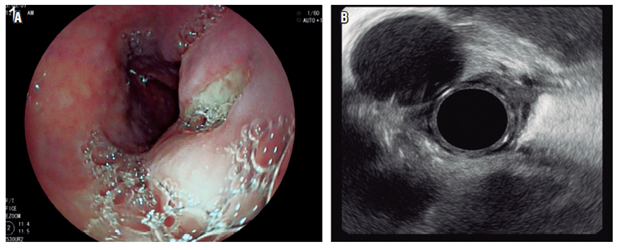

El control endosonográfico se llevó a cabo hacia el cuarto día posterior al procedimiento y se encontró un colapso completo de la lesión (Figura 4 A), asociado con una comunicación total con la luz esofágica en ausencia de residuos alimentarios (Figura 4 B).

Debido a su excelente evolución y a no presentar síntomas residuales, la paciente fue dada de alta con protector de mucosa (sucralfato), pero sin requerimiento de analgésico en casa. Se realizó seguimiento telefónico a los 10 días en el que se evaluó la tolerancia a la vía oral y la paciente manifestó que habían desaparecido por completo los síntomas de disfagia que la llevaron a consultar en un principio.